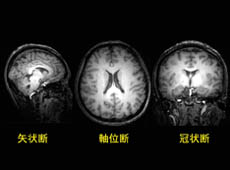

これまでに得られたいくつかの画像を紹介したい。図1は3次元形態画像から脳の3方向の断面を抽出した結果である。神経細胞が集積する灰白質(画像でも灰色に見える),神経細胞同士の連絡をする神経線維の束である白質(画像でも白っぽい)が明瞭に識別できる。この違いを用いて,両者を定量する方法も検討中である。また,図2では脳のほぼ中央両側に存在する側脳室と呼ばれる部位を抽出した(画像ではX字状の暗い部分)。上段が男性,下段が女性で左から右に年齢順に並べた。まだ,わずかな測定例ではあるが,年齢とともに脳室が拡大していく様子が明瞭に認められる。高精細の形態画像では,このほか男性と女性で性差があるといわれる脳梁の形態や厚さ,脳内のホルモン分泌器官である脳下垂体の形状にも注目している。図3は主に視覚に関与することが知られている脳の後ろの部分(後頭葉)に存在する代謝物を測定したスペクトルを示す。上段は陽子(1H)のスペクトルで,神経細胞のマーカーであるN-アセチルアスパラギン酸や,代表的な興奮性神経伝達物質であるグルタミン酸等の代謝物が認められる。下段はリン(31P)のスペクトルで,脳内のエネルギー代謝を司る高エネルギーのクレアチンリン酸やATPが明瞭に観測できる。これらのスペクトルは10分間の測定で得られ,世界で初めて両スペクトルを同時に得られるようになった。これらのスペクトルから脳の生理学的状態を表す情報が得られると期待している。